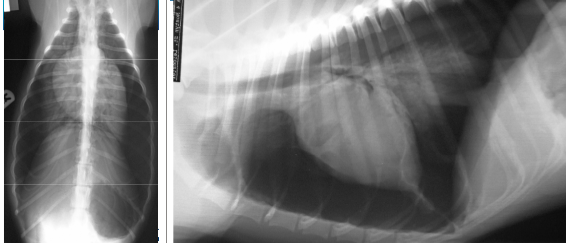

• whats the diagnosis?

pleural effusion